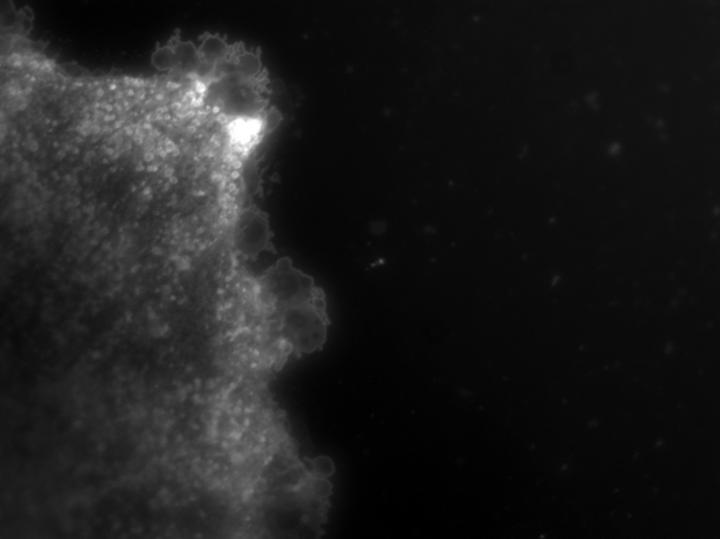

In their new study, described in Science Signaling April 13, Johns Hopkins researchers say there is evidence that vesicles or small (about the size of a virus), fat-like molecules and protein-filled sacks released from a type of immune cell in the brain called astrocytes travel through the bloodstream to the liver. The liver then instructs white blood cells to go to the site of injury in the brain.

He read earlier studies showing that the enzyme nSMase2 was required for forming and releasing exosomes. Exosomes form inside cell compartments and release outside the cell when these compartments fuse with the cell's surrounding membrane. Exosomes are surrounded by bits of cell membrane and filled with proteins and different types of the genetic material RNA.

To test that exosomes were the source of this brain to body communication, Haughey's research team isolated exosomes from the blood of mice four hours after injecting the cytokine IL-1b into brain and then injected the exosomes into the tail veins of different mice that had the cytokine and the nSMase-blocking drug altenusin already in their brains.

The researchers found that white blood cells in healthy mice who received exosomes from the blood of the mice with brain damage traveled to the site of brain injury, which the researchers say demonstrates that exosomes released from brain in response to damage alert the immune system to send the immune cell sentinels to the brain.